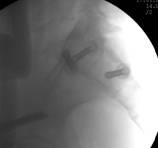

整个手术1小时内完成,通过术后CT影像证实3D打印导航模板引导骶髂螺钉置入安全、准确、创伤较小,手术时间短,患者也很快得到了较好的恢复。

术中C臂